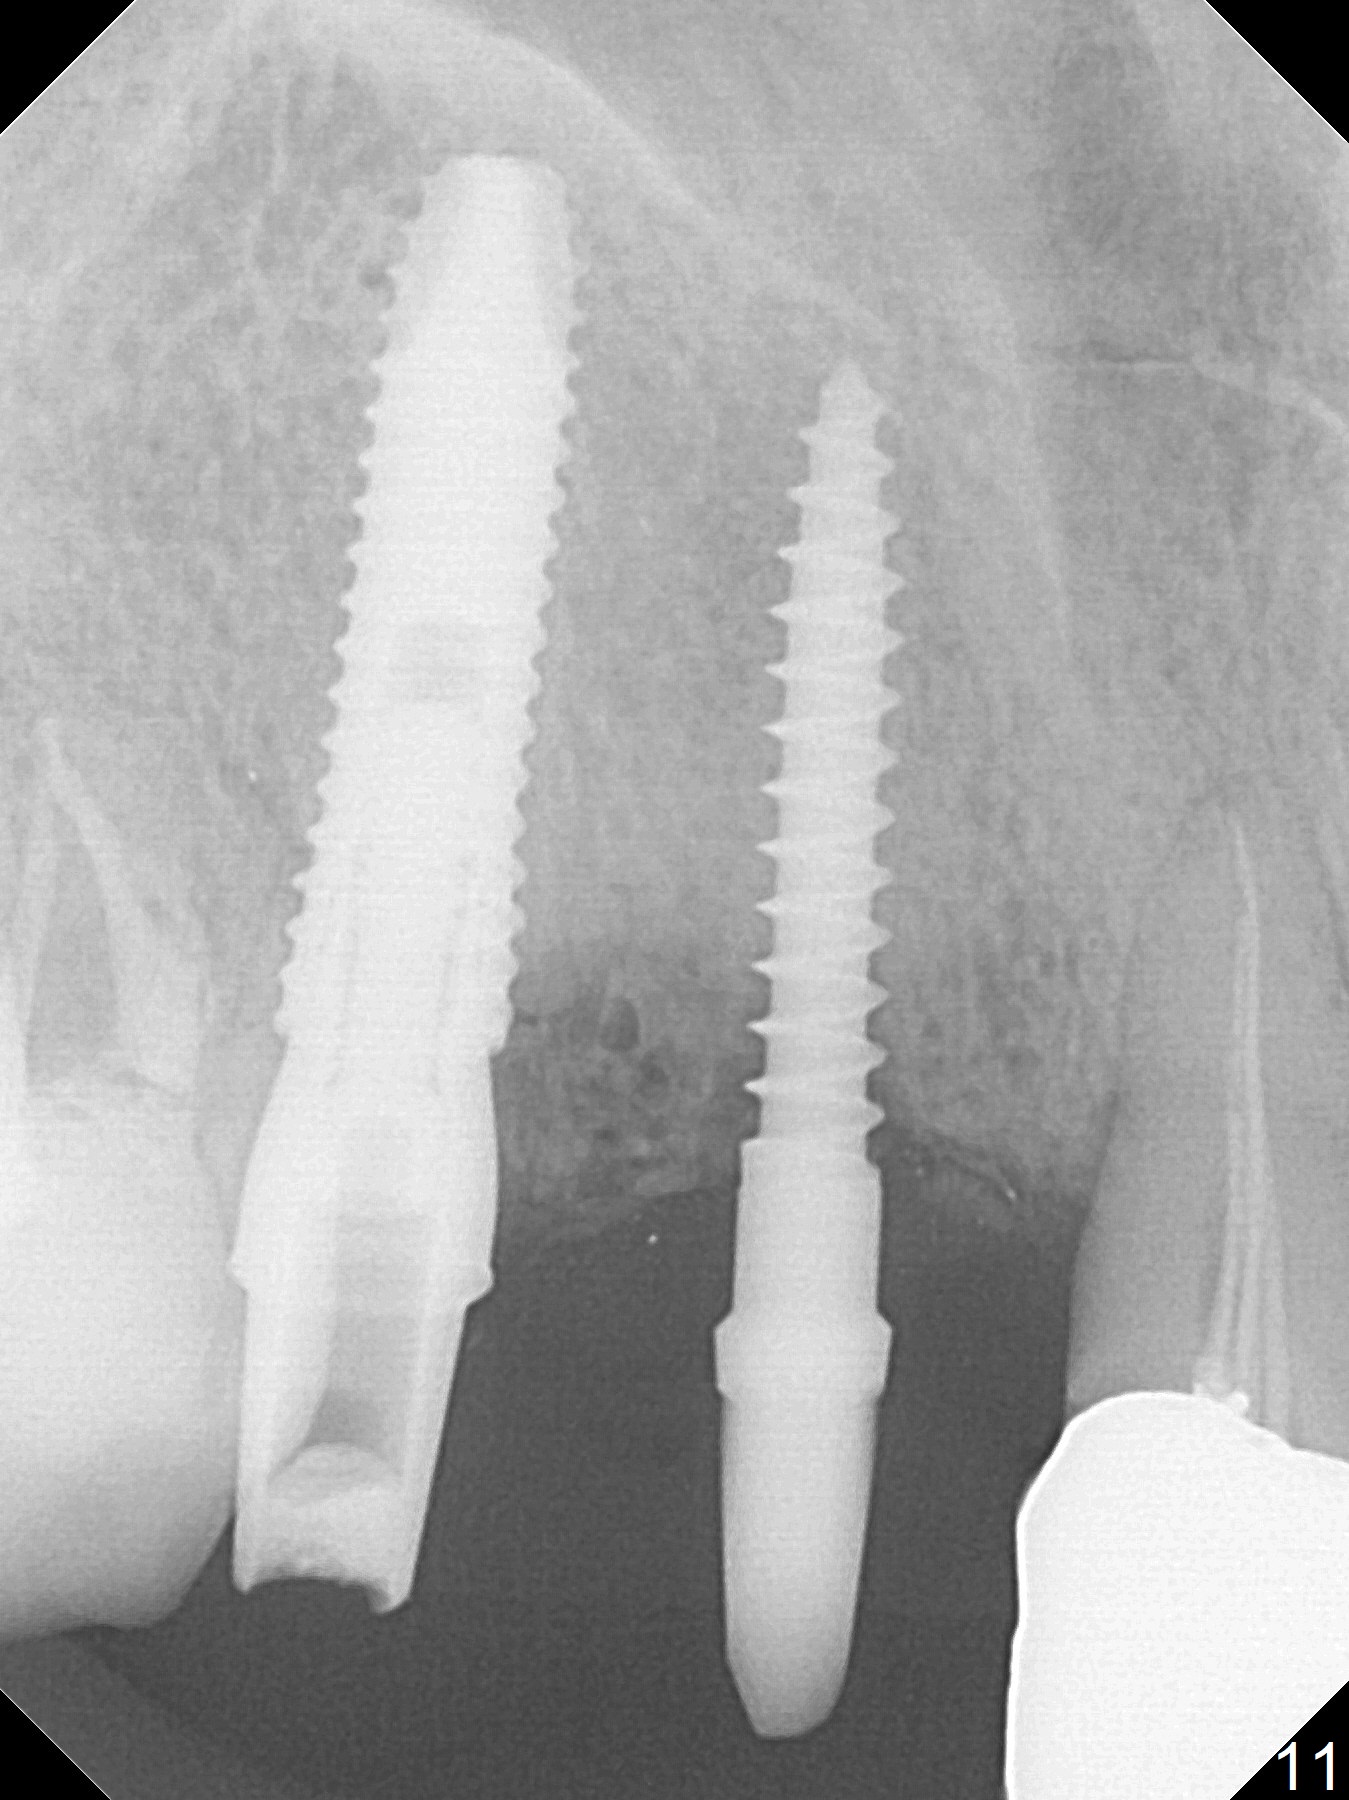

Since the ridge at #7 is ~ 4 mm, a 2.5x14 mm 1-piece implant is placed (Fig.8) after 1.2 mm (Fig.7), and 1.5 mm drills at 12 mm and 2 mm drill at 8 mm.  Later the implant is placed deeper (Fig.10).  There is no bone loss 7 or 12 months postop, respectively (Fig.11,12).  After Diode gingivectomy, there is papillary formation (Fig.13).  No provisional is provided after impression (with the abutment torqued at #6) for oral hygiene.  With access holes at #6 and 7, crowns are bonded with minimal residual cement (Fig.14 <, which is removed later).  There is no hard (Fig.15,16) or soft (Fig.17 *) atrophy 26 months postop, i.e., 13 months post cementation, due to the presence of socket shield (Fig.15 <, as compared to Fig.1).  In fact the tooth #8 has mobility and fremitus (short root/poor crown/root ratio, Fig.16); occlusal adjustment is done 13 months post cementation.  The crown is dislodged 2 years 1 month post cementation; a prefabricated post is being tried in (Fig.18).  There is no atrophy, bone loss or infection at #6 (with socket sheath (*)) or 7 two years 5 months post cementation (Fig.20-27).